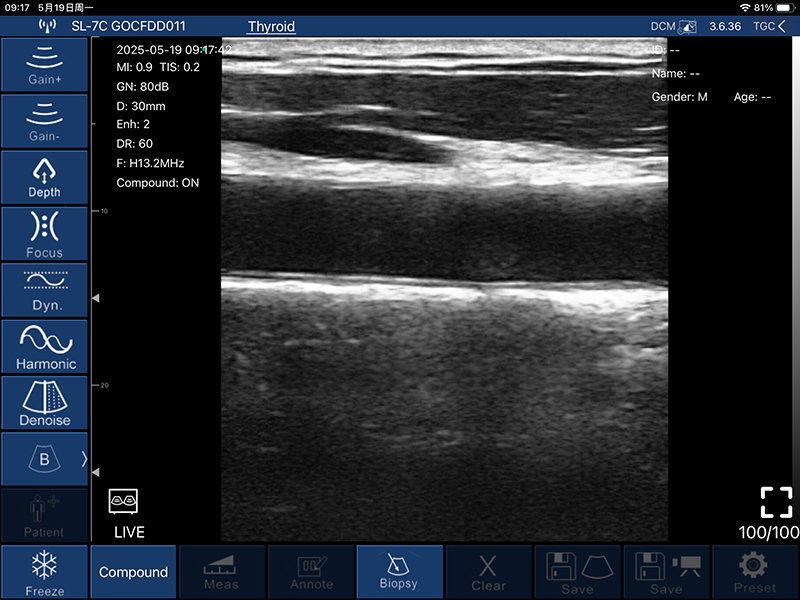

• 扫描深度:20/30/40/60mm,可调

• B模式

增益:30db-105db

降噪:0-1-2-3-4

动态范围: 40-50-60-70-80-90-100-110

• 穿刺辅助功能:平面内穿刺引导线功能,平面外穿刺引导与血管自动测量功能